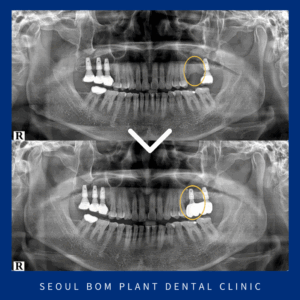

오금역보철치료 기존 보철물이 파절 되었다면

오금역보철치료 기존 보철물이 파절 되었다면     안녕하세요, 서울봄플란트치과 대표원장 송원섭입니다. 치아를 상실하게 되면 저작 기능이 저하될 뿐만 아니라 심미적인 문제도 발생할 수 있기 때문에 이러한 문제를 해결하기 위한 치료 방법으로 브릿지 보철물이 있습니다.     브릿지는 상실된 부위의 양쪽 더보기…